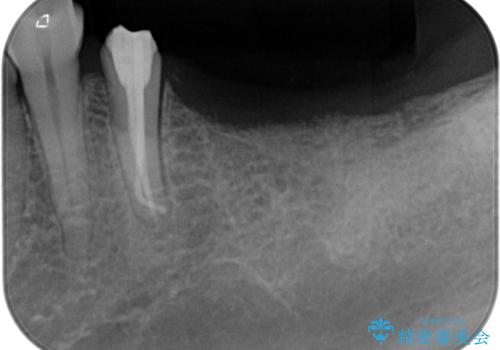

左下小臼歯は根管治療で対応する予定でしたが、診断のために歯肉を開いたところ頬側に垂直破折が認められたため、抜歯即時埋入インプラントによる補綴治療を選択することとしました。

右下は大臼歯部の歯は抜歯即時埋入インプラントにて、手前の歯は保存して補綴治療を行うこととしました。